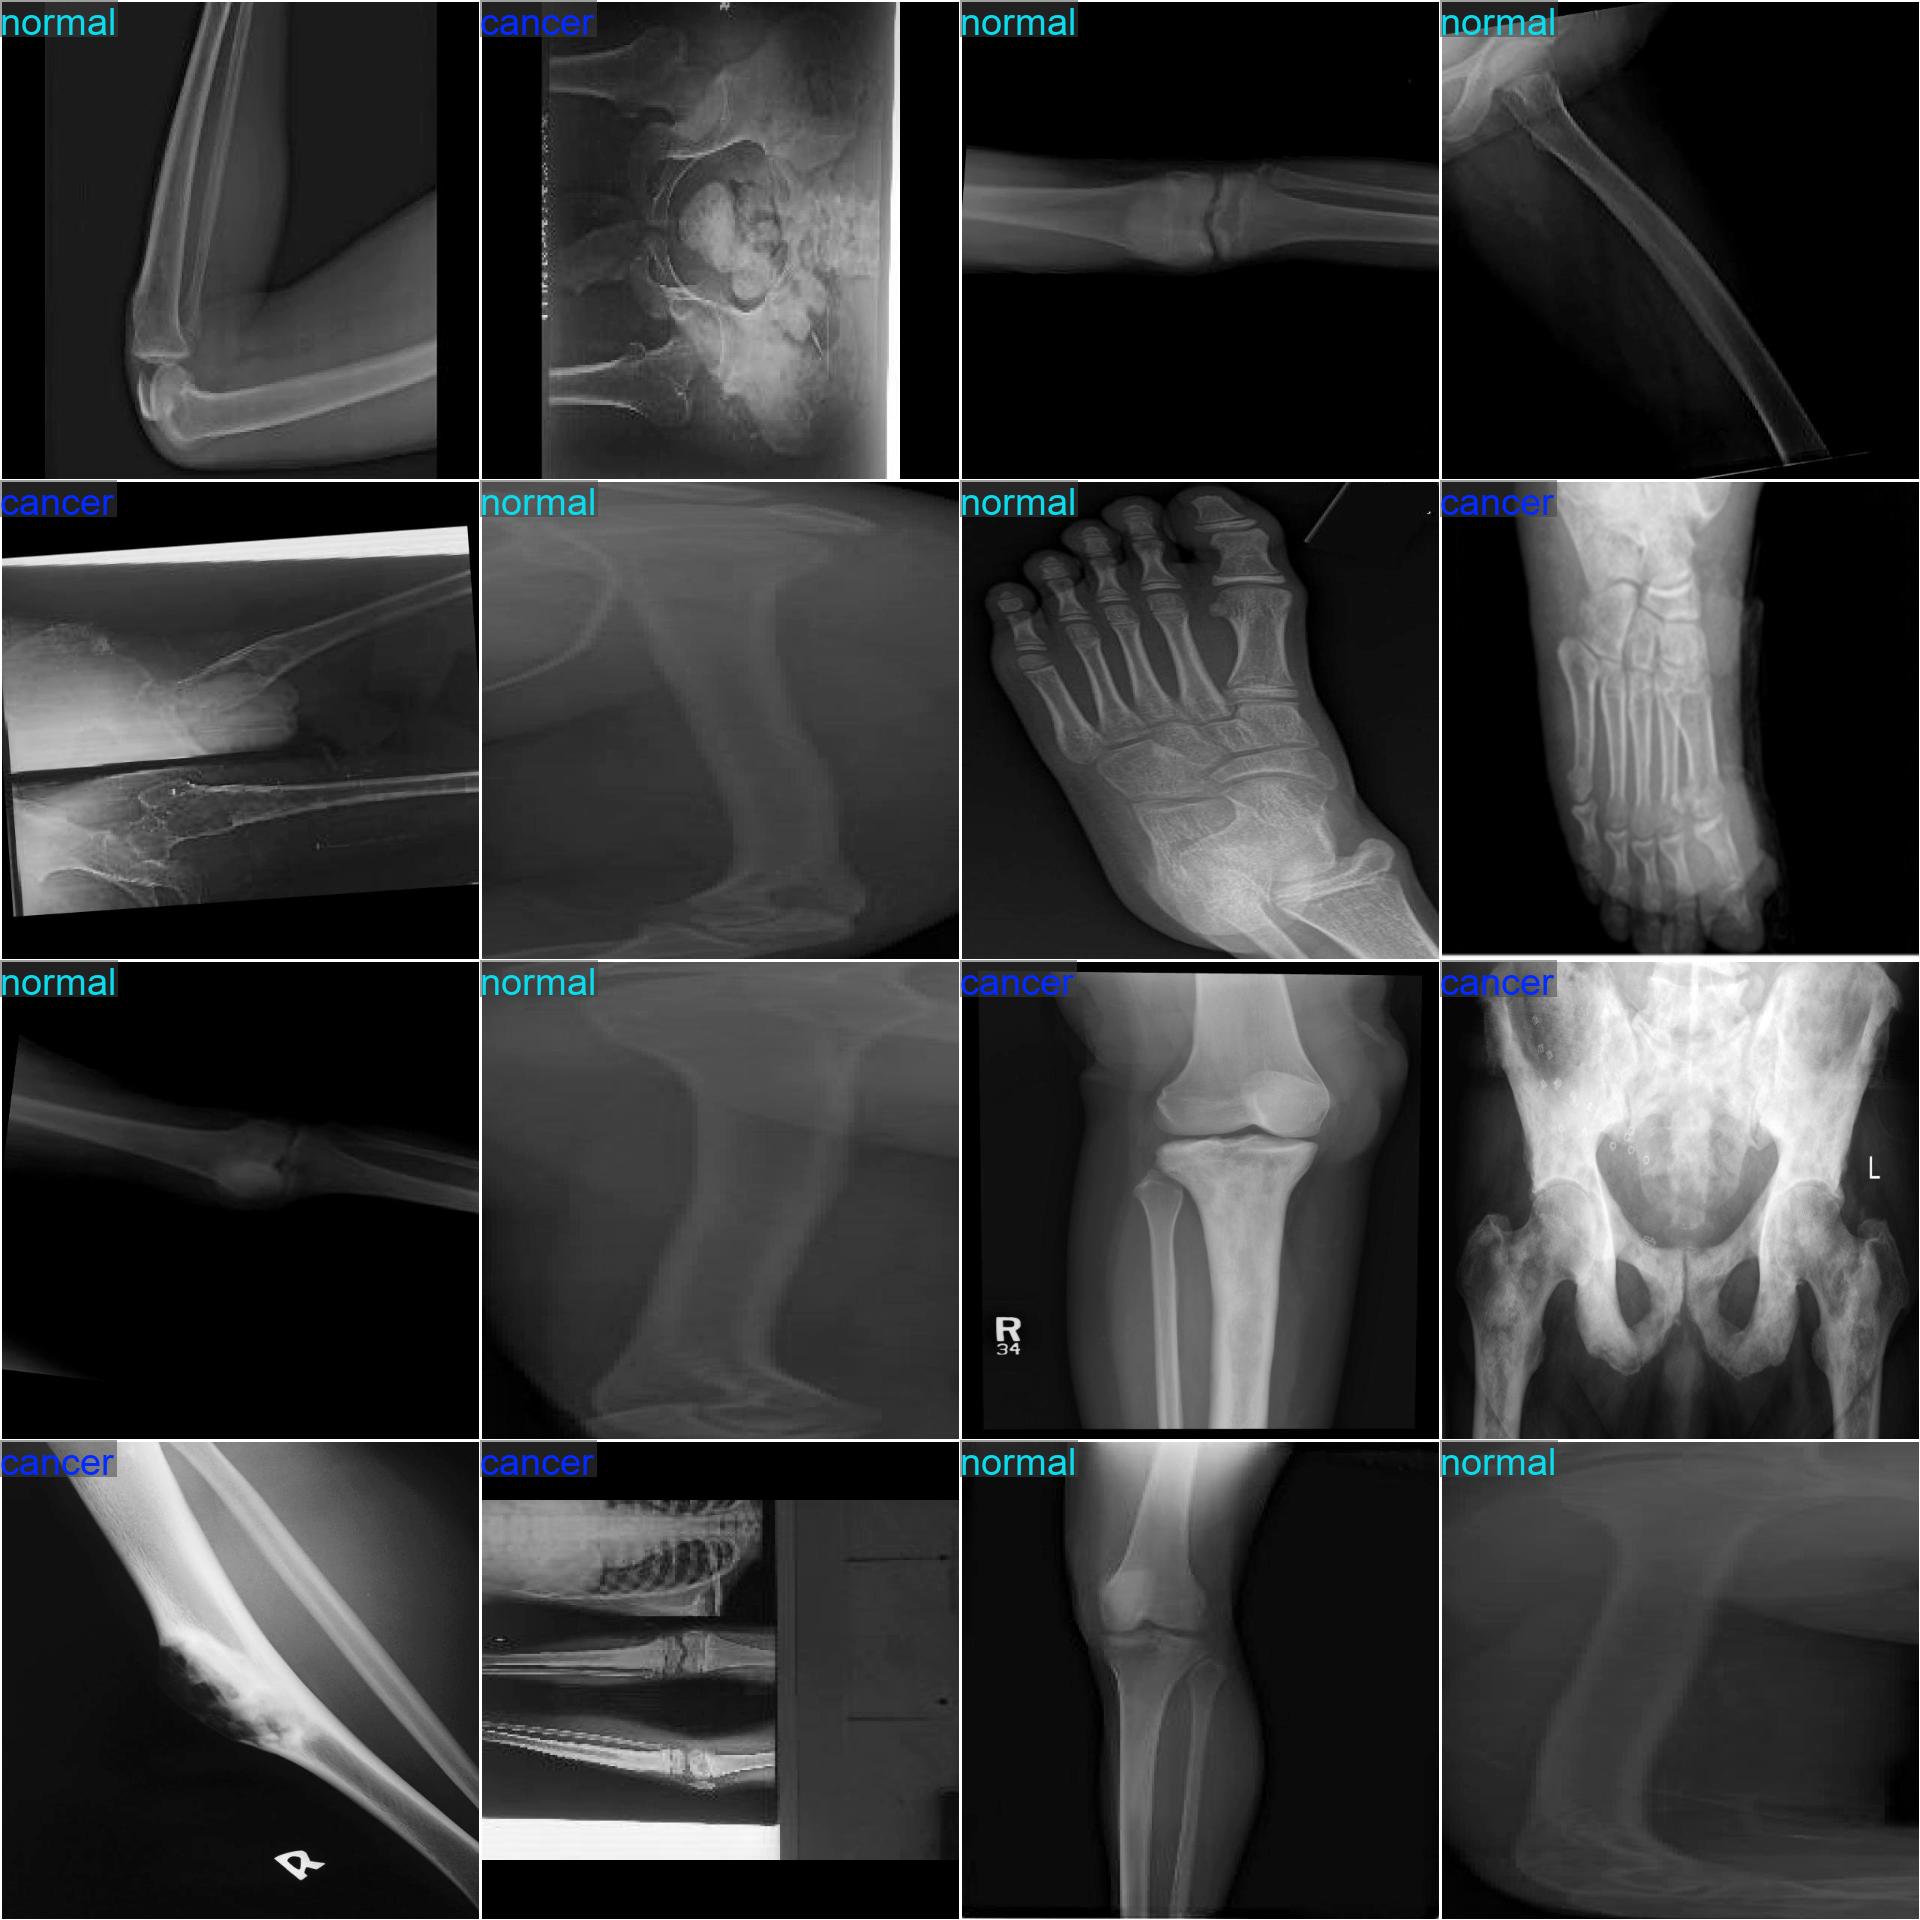

数据集缩略图截图

• 数据集介绍:骨癌检测图像分类数据集,真实临床采集高质量骨组织病理图片数据;

• **数据集类别:**carcer、normal;